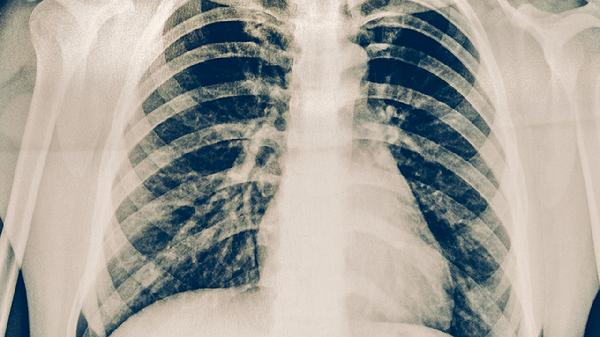

肺结核患者可遵医嘱使用异烟肼片、利福平胶囊、吡嗪酰胺片、乙胺丁醇片、链霉素注射液等抗结核药物。肺结核是由结核分枝杆菌感染引起的慢性传染病,需规范使用联合化疗方案,药物选择需根据患者肝肾功能、药物敏感性及治疗阶段调整。

肺结核患者需严格遵循早期、联合、适量、规律、全程的用药原则,完成6-9个月的标准疗程。治疗期间应保持高蛋白高维生素饮食,适当补充牛奶鸡蛋等优质蛋白,避免辛辣刺激性食物。定期复查胸部影像学和痰菌检查,出现药物不良反应及时就医调整方案,切忌自行停药或减量。注意隔离防护,咳嗽时掩住口鼻,痰液需消毒处理,保持居室通风换气。